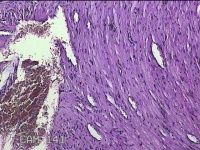

左足皮下结节

性别

女

年龄

31岁

临床诊断

皮下结节

一般病史

发现左足皮下结节,伴隐痛不适8个月余。

标本名称

大体所见

灰白粉红色结节1x0.8x0.3cm一个,表面光滑,切面灰白粉红色,质软。